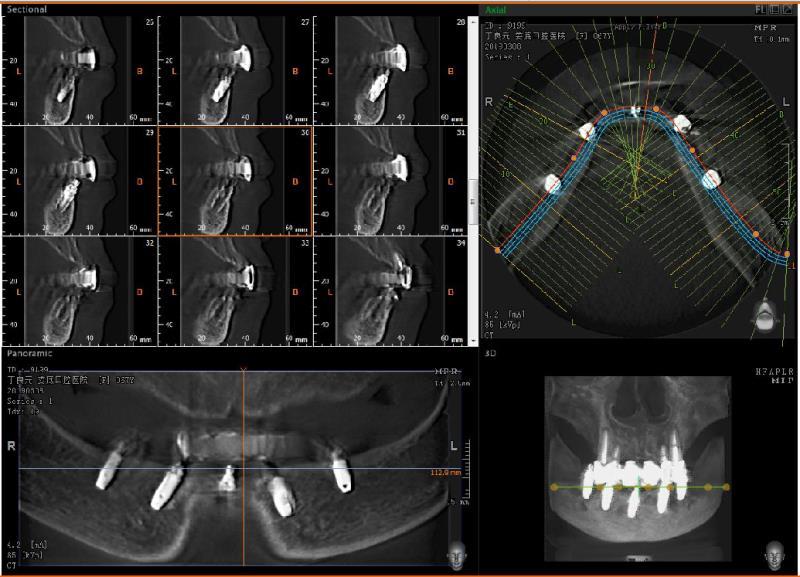

丁女士在我院解決多年缺牙困擾

姓名:丁女士

年齡:67

職業(yè):全職太太

主訴:上下頜多數(shù)牙齒缺失多年,吃不好飯,影響咀嚼和消化功能,近兩年身體體重逐漸消瘦,急需鑲牙解決問(wèn)題。

檢查:口內(nèi)檢查:右上2、右上3已齲壞,叩(+),無(wú)松動(dòng),右上2、3齲壞,叩(+),無(wú)松動(dòng),左下3、4牙體缺損,松動(dòng),右下4三度松動(dòng),其余牙齒缺失,

診斷:上下頜牙列缺損

治療方案:右上2、3,左上2、3根管治療及樁加前牙連冠修復(fù),上頜后牙局部可摘義齒修復(fù),下頜拔除殘留牙齒,all-on-5種植,即刻修復(fù)。